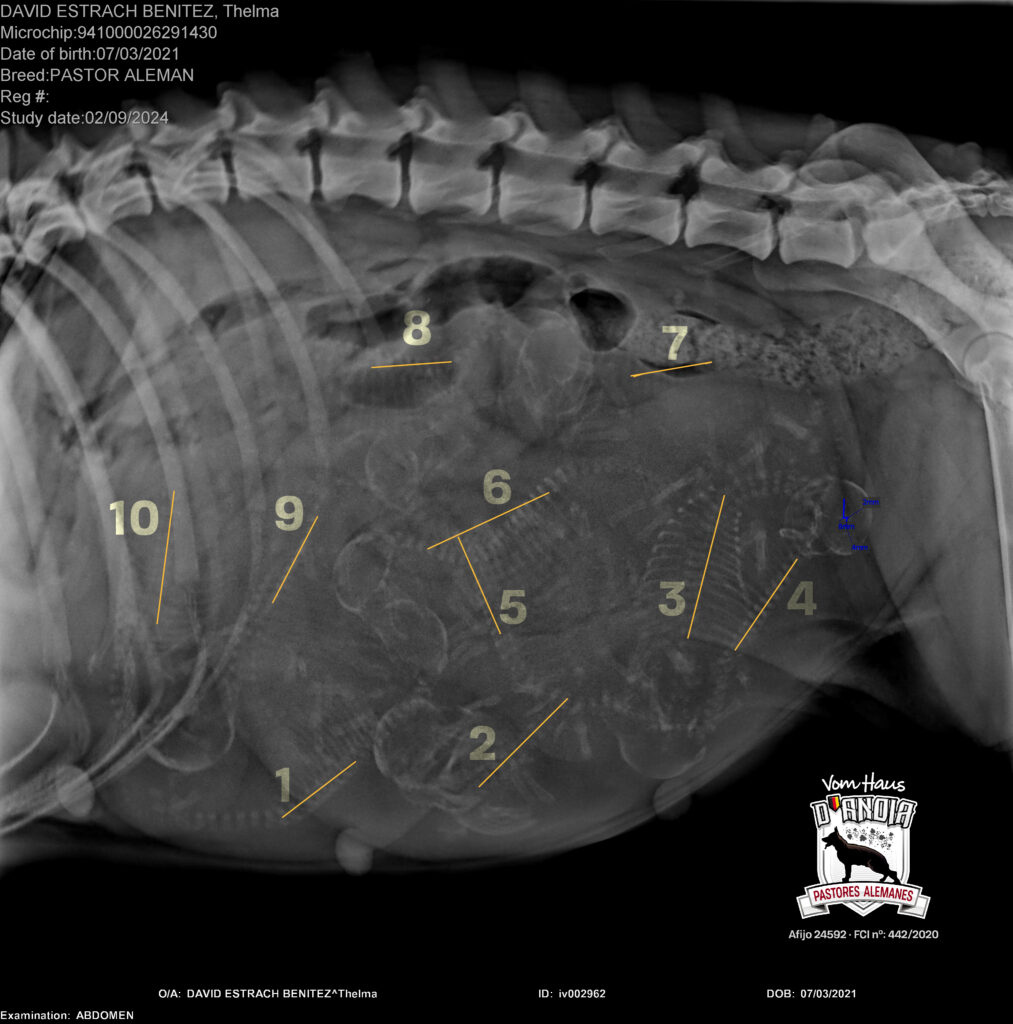

Thelma (Turca de Usurbe)